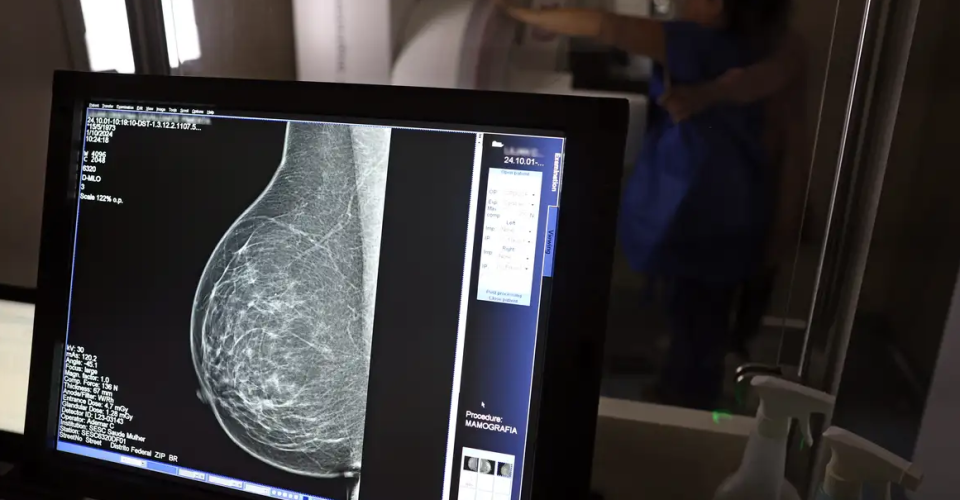

Cerca de 77 mil mulheres aguardam mamografia pelo SUS

Em junho deste ano, 77.243 brasileiras aguardavam por uma mamografia no SUS (Sistema Único de Saúde). Santa Catarina é o estado com mais mulheres na fila de espera, cerca de 17 mil. Em seguida, aparecem São Paulo (15 mil) e Rio de Janeiro (12,5 mil). Juntos, os três estados somam 56% do total de pacientes à espera do principal exame para detecção do câncer de mama. Os dados foram divulgados nesta quinta-feira (31) pelo CBR (Colégio Brasileiro de Radiologia e Diagnóstico por Imagem).

Segundo a entidade, em alguns locais do país, o tempo de espera por uma mamografia na rede pública pode chegar a 80 dias. O exame, quando realizado em tempo hábil, permite a detecção precoce de alterações mamárias, aumentando as chances de tratamento bem-sucedido e reduzindo a necessidade de intervenções invasivas e onerosas. “Os números revelam parte da sobrecarga no SUS e devem ser levados em conta, especialmente pelos recém-eleitos nas eleições municipais, na formulação e manutenção de políticas de saúde pública”, avaliou o CBR.